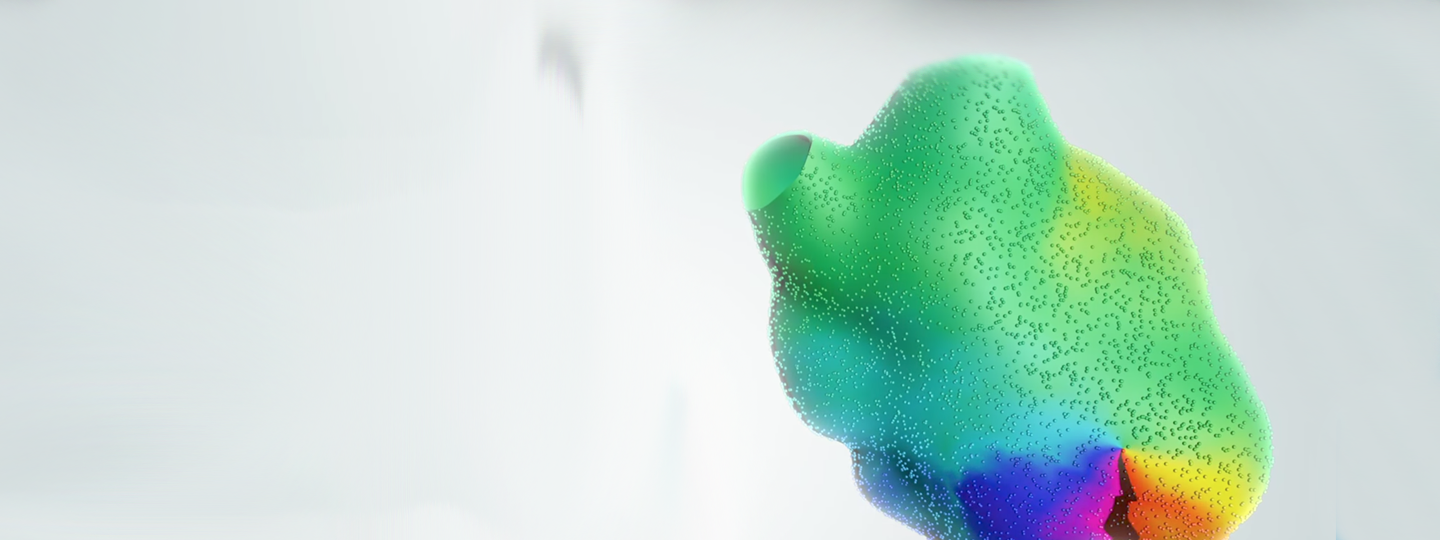

RHYTHMIA HDx™ Mapping System

The RHYTHMIA HDx™ Mapping System offers industry-defining cardiac mapping, a powerful analysis toolset designed to streamline targeting and clinical decision-making, and unique insights into tissue substrate and lesion formation during RF ablation. Taken together, the elements of RHYTHMIA HDx provide unrivalled speed and precision in cardiac mapping and enhanced guidance in ablation delivery, helping physicians optimize treatment approaches and patient outcomes.

Designed to intelligently capture and automatically annotate high-fidelity EGM signals, RHYTHMIA HDx provides a more complete picture of cardiac electrical pathways. The system combines advanced signal-processing hardware, a cardiac mapping algorithm that can rapidly process unprecedented amounts of data, and the INTELLAMAP ORION™ High-Resolution Mapping Catheter. Its small, flat, printed electrodes capture signal only at the electrode-tissue interface, significantly reducing signal noise to a low 0.01mV. The result is an enhanced clarity and depth of detail in cardiac mapping and greater confidence in tailoring treatment.

Designed to intelligently capture and automatically annotate high-fidelity EGM signals, RHYTHMIA HDx provides a more complete picture of cardiac electrical pathways. The system combines advanced signal-processing hardware, a cardiac mapping algorithm that can rapidly process unprecedented amounts of data, and the INTELLAMAP ORION™ High-Resolution Mapping Catheter. Its small, flat, printed electrodes capture signal only at the electrode-tissue interface, significantly reducing signal noise to a low 0.01mV. The result is an enhanced clarity and depth of detail in cardiac mapping and greater confidence in tailoring treatment.